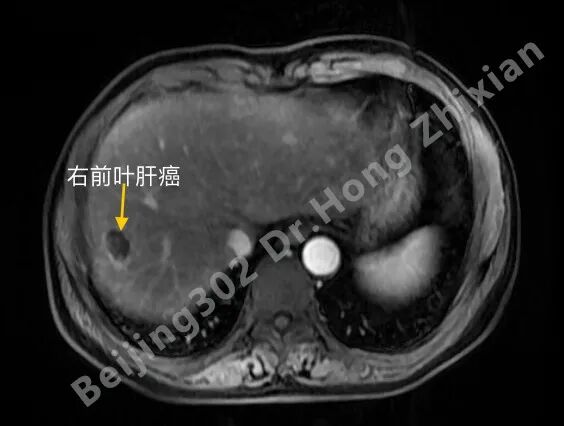

临床随笔丨肝癌术前新辅助治疗:“更优选择”还是“过度治疗”?